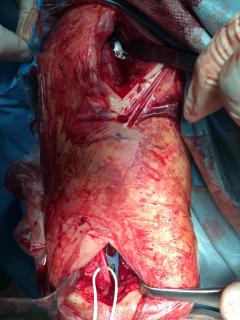

Κατάγματα μακρών οστών άνω και κάτω άκρου

Τα εν λόγω κατάγματα είναι αρκετά συνηθισμένα και συχνά συμβαίνουν μετά από τροχαία ατυχήματα ή πτώση από ύψος. Παρατηρείται εξαιρετικά μεγάλη ποικιλία στη μορφή τους, κατα κανόνα όμως είναι σοβαρά και πολλές φορές ανοικτά – δηλ με τραύμα στο σημείο του κατάγματος – κάτι που αυξάνει τον κίνδυνο λοίμωξης και επιβαρύνει την πορεία της θεραπείας. Στα κατάγματα των άνω άκρων ενδέχεται να υπάρξει και τραυματισμός νεύρων, που χρειάζεται επίσης αντιμετώπιση.

Με τα σύγχρονα μέσα που διαθέτουμε, όλα σχεδόν αυτά τα κατάγματα πρέπει να αντιμετωπίζονται χειρουργικώς. Υπάρχει πληθώρα υλικών οστεοσύνθεσης (πλάκες διαφόρων τύπων, ενδομυελικοί ήλοι, συστήματα εξωτερικής οστεοσύνθεσης) που είναι διαθέσιμα και επαφίεται στην εμπειρία του χειρουργού η επιλογή.

Οπως και άλλοι εξοικειωμένοι χειρουργοί διεθνώς, χρησιμοποιώ τεχνικές ελάχιστης παρέμβασης (Minimal Invasive Surgery), δηλαδή μικρές τομές, επειδή έτσι το χειρουργικό τραύμα είναι ελάχιστο, με αποτέλεσμα ταχύτερη επούλωση. Ταχύτερη πώρωση των καταγμάτων, ταχύτερη κινητοποίηση.

Περίπτωση 3ου ασθενούς